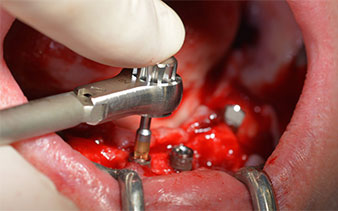

This corresponds to the next preset position in the Implantmed. Here we see the W&H contra-angle handpiece being held at a 45° angle to mesiocaudal in the region of 45 in order to preserve the mental nerve. The mental foramen is used as the anatomic reference for all drilling in this region. The subsequent holes were drilled at a reduced speed of 300 rpm (Fig. 10 and 11).

The next programmed setting is already for placement of the implants. In our practice we usually employ a torque of 32 Ncm to place the implants (Fig. 12 and 13).

High primary stability is an absolute requirement for an immediate restoration. In order to achieve this, the hole was not tapped in this case. The W&H Implantmed drill unit used here is equipped with a suitable special mode for this, which can also be directly selected and is indispensable for many indications. The final revolutions when placing the implants exceeded the value of 32 Ncm and were performed by hand. In such cases, we recommend utilizing the implants’ self-tapping function and twisting the implants backwards and forwards several times. This allows the implant to approach the final position gradually without exerting excessive pressure on the bone (Fig. 14).